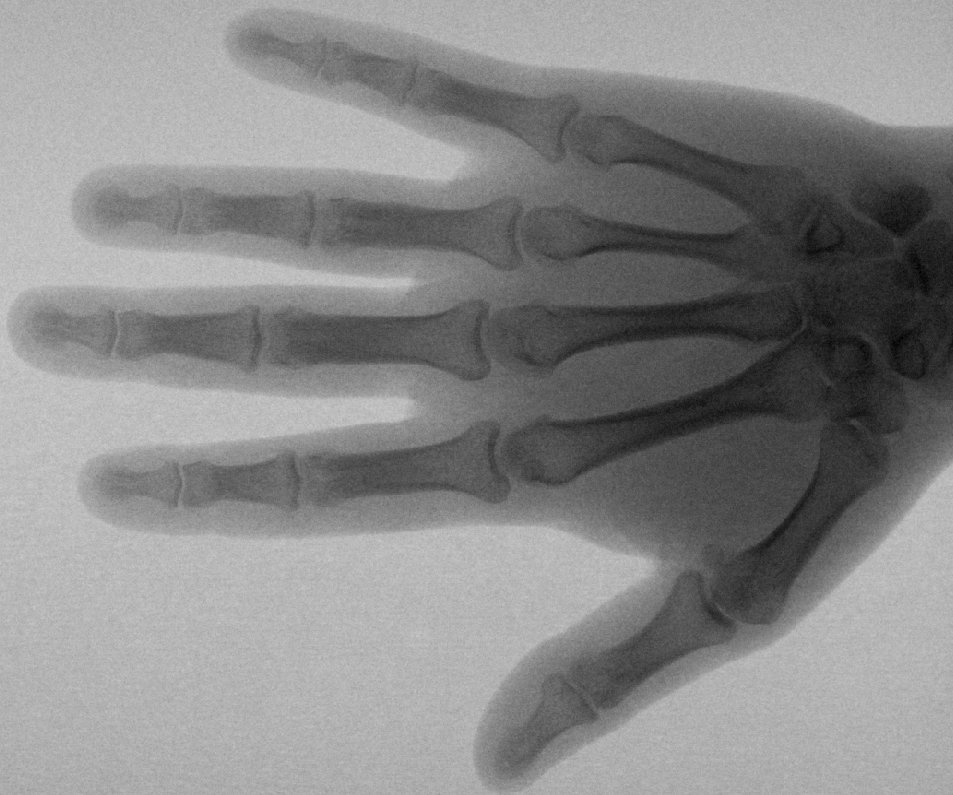

История знает немало гениальных открытий, сделанных случайно. К таковым относится обнаружение Х-лучей. Они имеют такое огромное значение для медицины, что стали синонимом слову «диагноз». И это не единственная область их применения. Человечество благодарно немецкому ученому, сделавшему миру подарок, значение которого невозможно переоценить, и помнит дату, когда физик Вильгельм Рентген открыл «рентгеновские лучи».

8 ноября 1895 года ректор университета в баварском городе Вюрцбурге до поздней ночи работал в лаборатории, где уже несколько месяцев проводил эксперименты с катодными лучами. Погасив свет, он заметил в углу свечение, исходившее от экрана, заполненного цианидом бария. Проверив все приборы, ученый обнаружил невыключенную вакуумную трубку. Исправив оплошность, физик увидел, что свечение исчезло, но появилось при повторном включении прибора. Экспериментатор забыл про сон и усталость и всю ночь занимался опытами. В результате были открыты доселе неизвестные икс-лучи, способные проходить через физическое тело, оставляя на экране его световой рельеф. Чтобы понять их природу, 3 месяца Вильгельм практически жил в лаборатории. Затем еще несколько лет понадобилось, чтобы понять пользу открытия.